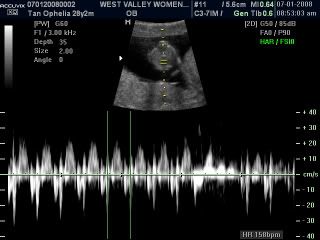

Beanie's heartbeat at 158bpm, his heartbeat is so fast... daddy and me just smile...